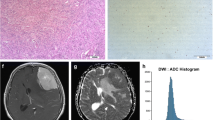

This prospective study comprised 69 meningioma patients who underwent preoperative MRI including T1 mapping and DWI. The histogram metrics, including mean, median, maximum, minimum, 10th percentiles (C10), 90th percentiles (C90), kurtosis, skewness, and variance, of T1 and apparent diffusion coefficient (ADC) values were extracted from the whole tumour and peritumoural oedema using FeAture Explorer. The Mann-Whitney U test was used for comparison between low- and high-grade tumours. Receiver operating characteristic (ROC) curve and logistic regression analyses were performed to identify the differential diagnostic performance. The Kruskal-Wallis test was used to further classify meningioma subtypes. Spearman’s rank correlation coefficients were calculated to analyse the correlations between histogram parameters and Ki-67 expression.

High-grade meningiomas showed significantly higher mean, maximum, C90, and variance of T1 (p = 0.001–0.009), lower minimum, and C10 of ADC (p = 0.013–0.028), compared to low-grade meningiomas. For all histogram parameters, the highest individual distinctive power was T1 C90 with an AUC of 0.805. The best diagnostic accuracy was obtained by combining the T1 C90 and ADC C10 with an AUC of 0.864. The histogram parameters differentiated 4/6 pairs of subtype pairs. Significant correlations were identified between Ki-67 and histogram parameters of T1 (C90, mean) and ADC (C10, kurtosis, variance).